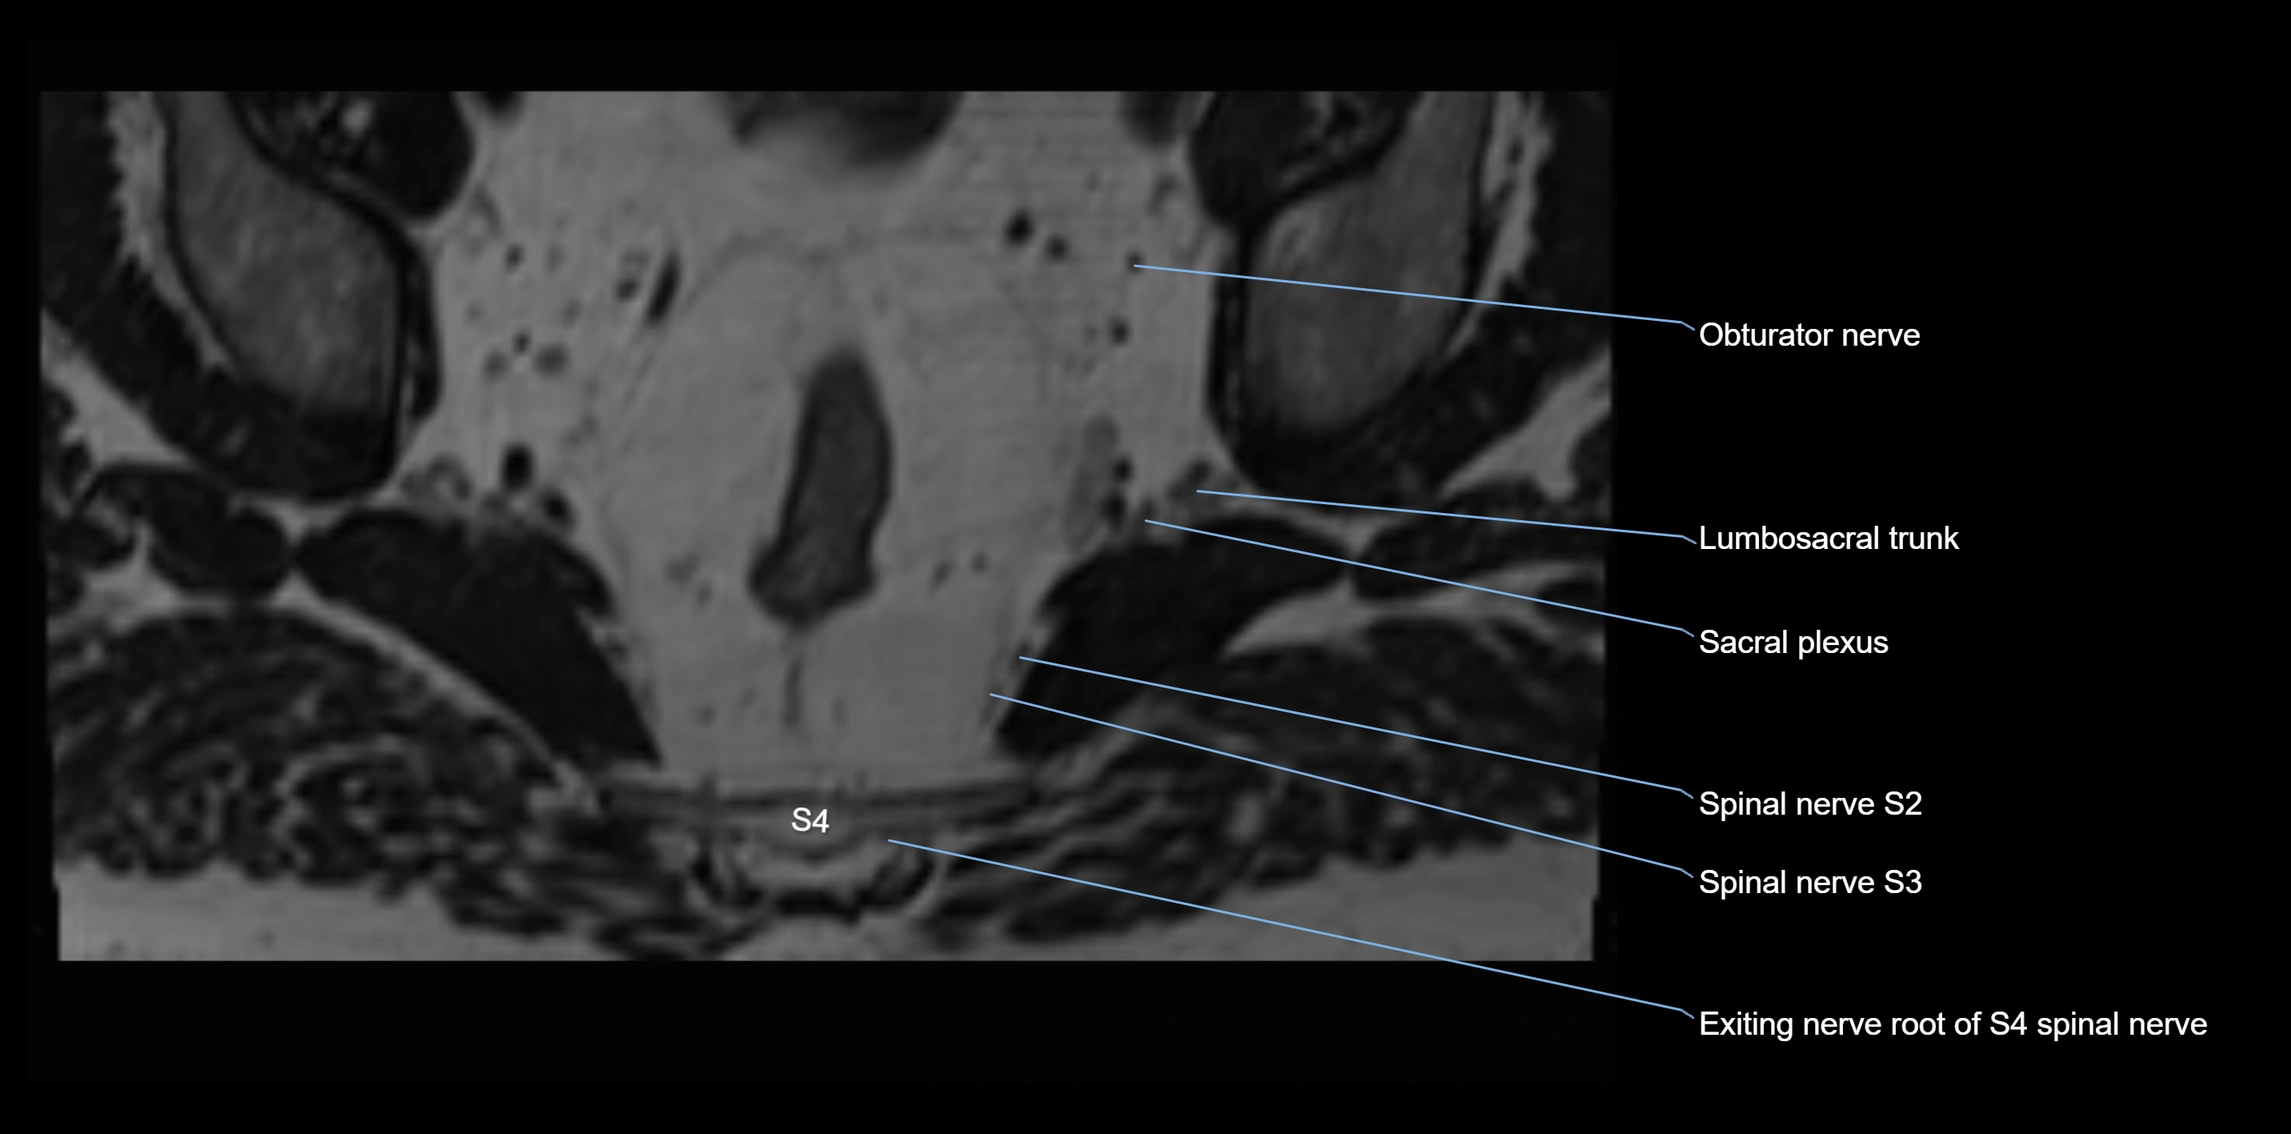

MRI Appearance

T1-weighted images:

• Nerve appears as a very thin low-to-intermediate signal intensity structure

• Surrounded by bright fat, aiding visualization

T2-weighted images:

• Nerve shows intermediate to mildly hyperintense signal compared to muscle

• Pathological involvement appears brighter

STIR (Short Tau Inversion Recovery):

• Normal nerve appears dark

• Inflamed or entrapped nerve appears bright hyperintense

T1 Fat-Sat Post-Contrast:

• Normal nerve enhances minimally

• Pathologic nerve (neuritis, entrapment, tumor infiltration) shows focal or diffuse enhancement

3D T2 SPACE / CISS:

• Nerve appears intermediate to mildly hyperintense compared to muscle

• Surrounded by bright fat or CSF, improving visualization

• Best sequence for mapping small pelvic nerves such as the anococcygeal

MRI image

image